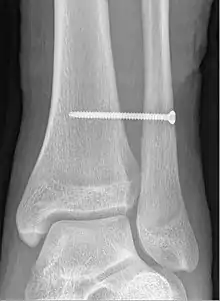

X-ray of a syndesmotic screw in place.

A syndesmotic screw designed to replace the inferior tibiofibular articulation that fix the tibia and fibula together at the lower joint, is 5–6 cm long and made of a stainless, solid metal.